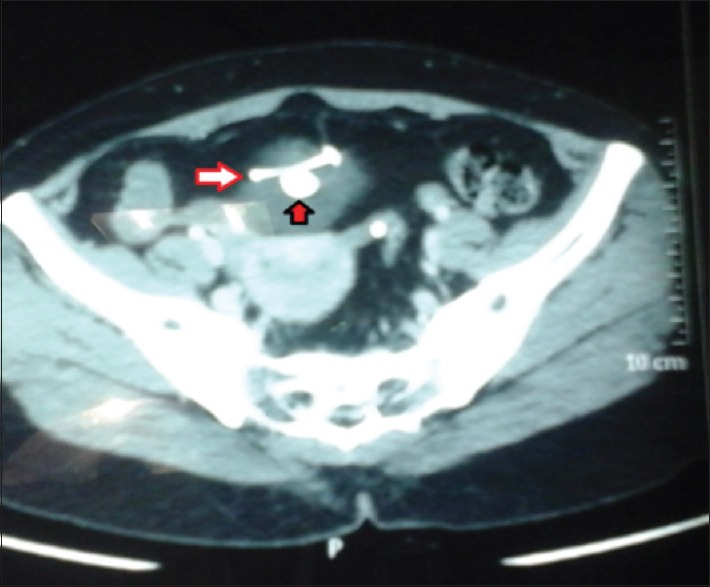

最常用的长期可逆女性避孕方法是宫内节育器(IUCD)。然而,它的使用与文献记载的并发症有关。子宫穿孔,虽然罕见,但可以说是所有这些并发症中最重要的手术。我们报告一例48岁的4+0(4活着)妇女,17年前植入了IUCD,此后有两个孩子,却忘记了她有这个装置。随后,宫内节育器经膀胱穹窿移位至腹膜腔,膀胱内宫内节育器尾线周围形成结石,引起反复尿路感染。这种“衣领钉”效应使得单独的膀胱镜或腹腔镜手术不成功,需要联合手术。本病例报告强调需要联合腹腔镜和膀胱镜的方法在检索的不寻常的表现易位宫内节育器。

The most commonly used long-term reversible female contraception is intrauterine contraceptive device (IUCD). Its use is however associated with documented complications. Uterine perforation, though rare, is arguably the most surgically important of all these complications. We report a case of a 48-year-old para 4+0 (4 alive) woman who had IUCD insertion 17 years earlier and had forgotten she had the device having had two children thereafter. The IUCD was subsequently translocated through the dome of the bladder into the peritoneal cavity with calculus formation around the tail and thread of the IUCD in the urinary bladder causing recurrent urinary tract infection. This "Collar Stud" effect made either cystoscopic or laparoscopic retrieval alone unsuccessful necessitating a combined approach. This case report highlights the need for a combined laparoscopic and cystoscopic approach in the retrieval of the unusual presentation of translocated IUCD.